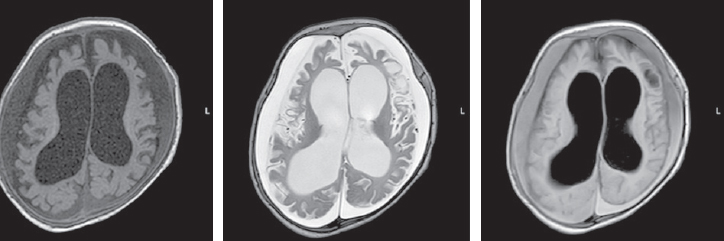

The child’s condition remained critical, with impaired consciousness, extension contractures in the elbow and knee joints, and non-epileptic paroxysmal states, such as bronchospasm and apnea persisting. Startle reflexes were pronounced and with any tactile stimulation, startle (generalized myoclonus) was registered. With the progression of neurological disorders, an increase in the cystic-atrophic changes was noted and hydrocephalus was formed. The data of MRI over a time, performed at the age of four months, are presented in Fig. 3.

Fig. 3. Magnetic resonance imaging of a patient at the age of 4 months. Axial sections, T1 VI, T2 VI, Flair. There is a negative dynamics in the form of cystic-atrophic changes in the large hemispheres of the brain with the formation of atrophic hydrocephalus. The appearance of symmetrical subshell clusters in the form of subdural hygromas

Рис. 3. Магнитно-резонансная томограмма пациента в возрасте 4 мес. Аксиальные срезы, Т1ВИ, Т2 ВИ, Flair. Наблюдается отрицательная динамика в виде кистозно-атрофических изменений в больших полушариях головного мозга с формированием атрофической гидроцефалии. Появление симметричных подоболочечных скоплений в виде субдуральных гигром

The MRI, performed at seven months of child’s age, revealed a moderate increase in the severity of atrophic changes. Bilateral cystic encephalomalacia of the cerebral hemispheres as well as atrophic hydrocephalus with dilatation of the external and internal cerebrospinal fluid spaces occured. Bilateral chronic subdural hematomas (hygromas) progressed (Fig. 4).

Fig. 4. Magnetic resonance imaging of a patient at the age of 7 months. Axial sections, T1 VI, T2 VI, Flair. There is a bilateral cystic encephalomalacia of the large hemispheres of the brain, atrophic expansion of the external and internal liquor spaces – a moderate increase in the severity of changes. Bilateral chronic subdural hematomas (hygromas) – a moderate increase in fluid volume

Рис. 4. Магнитно-резонансная томограмма пациента в возрасте 7 мес. Аксиальные срезы, Т1ВИ, Т2 ВИ, Flair. Отмечается билатеральная кистозная энцефаломаляция больших полушарий головного мозга, атрофическое расширение наружных и внутренних ликворных пространства — умеренное нарастание степени выраженности изменений. Двусторонние хронические субдуральные гематомы (гигромы) — умеренное увеличение объема жидкости